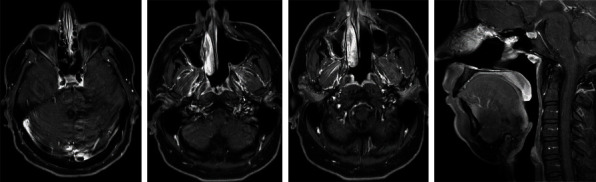

Sarcoma with BCOR genetic alteration is an exceptionally rare and emerging subtype of sarcoma. It is categorized into two types: BCOR-related gene fusions such as BCOR::CCNB3 sarcomas and other BCOR-rearranged sarcoma and sarcomas with internal tandem duplication of BCOR genes such as infantile undifferentiated round cell sarcomas and primitive myxoid mesenchymal tumors of infancy. BCOR::CCNB3 sarcomas predominantly arise in bone rather than soft tissue and exhibit a higher occurrence in children and adolescent males, whereas sarcomas with BCOR internal tandem duplication show a wider age range but usually arise in the first year of life. Due to their rarity, there is ongoing debate and uncertainty regarding the best treatment approach, with a lack of specific clinical trials addressing these tumors. In this report, we present a unique case of sarcoma with internal tandem duplication of BCOR gene originating in the nasal region. The tumor was successfully and completely resected using the standard VDC-IE chemotherapy protocol, resulting in an unprecedented 100 percent tumor necrosis. The patient has completed the protocol and remains recurrence-free 13 months after diagnosis. This case suggests potential efficacy of the standard VDC-IE protocol in achieving remarkable responses in BCOR rearrangement sarcomas, including the internal tandem duplication subtype. However, further studies are needed to determine the optimal treatment strategies for this disease.